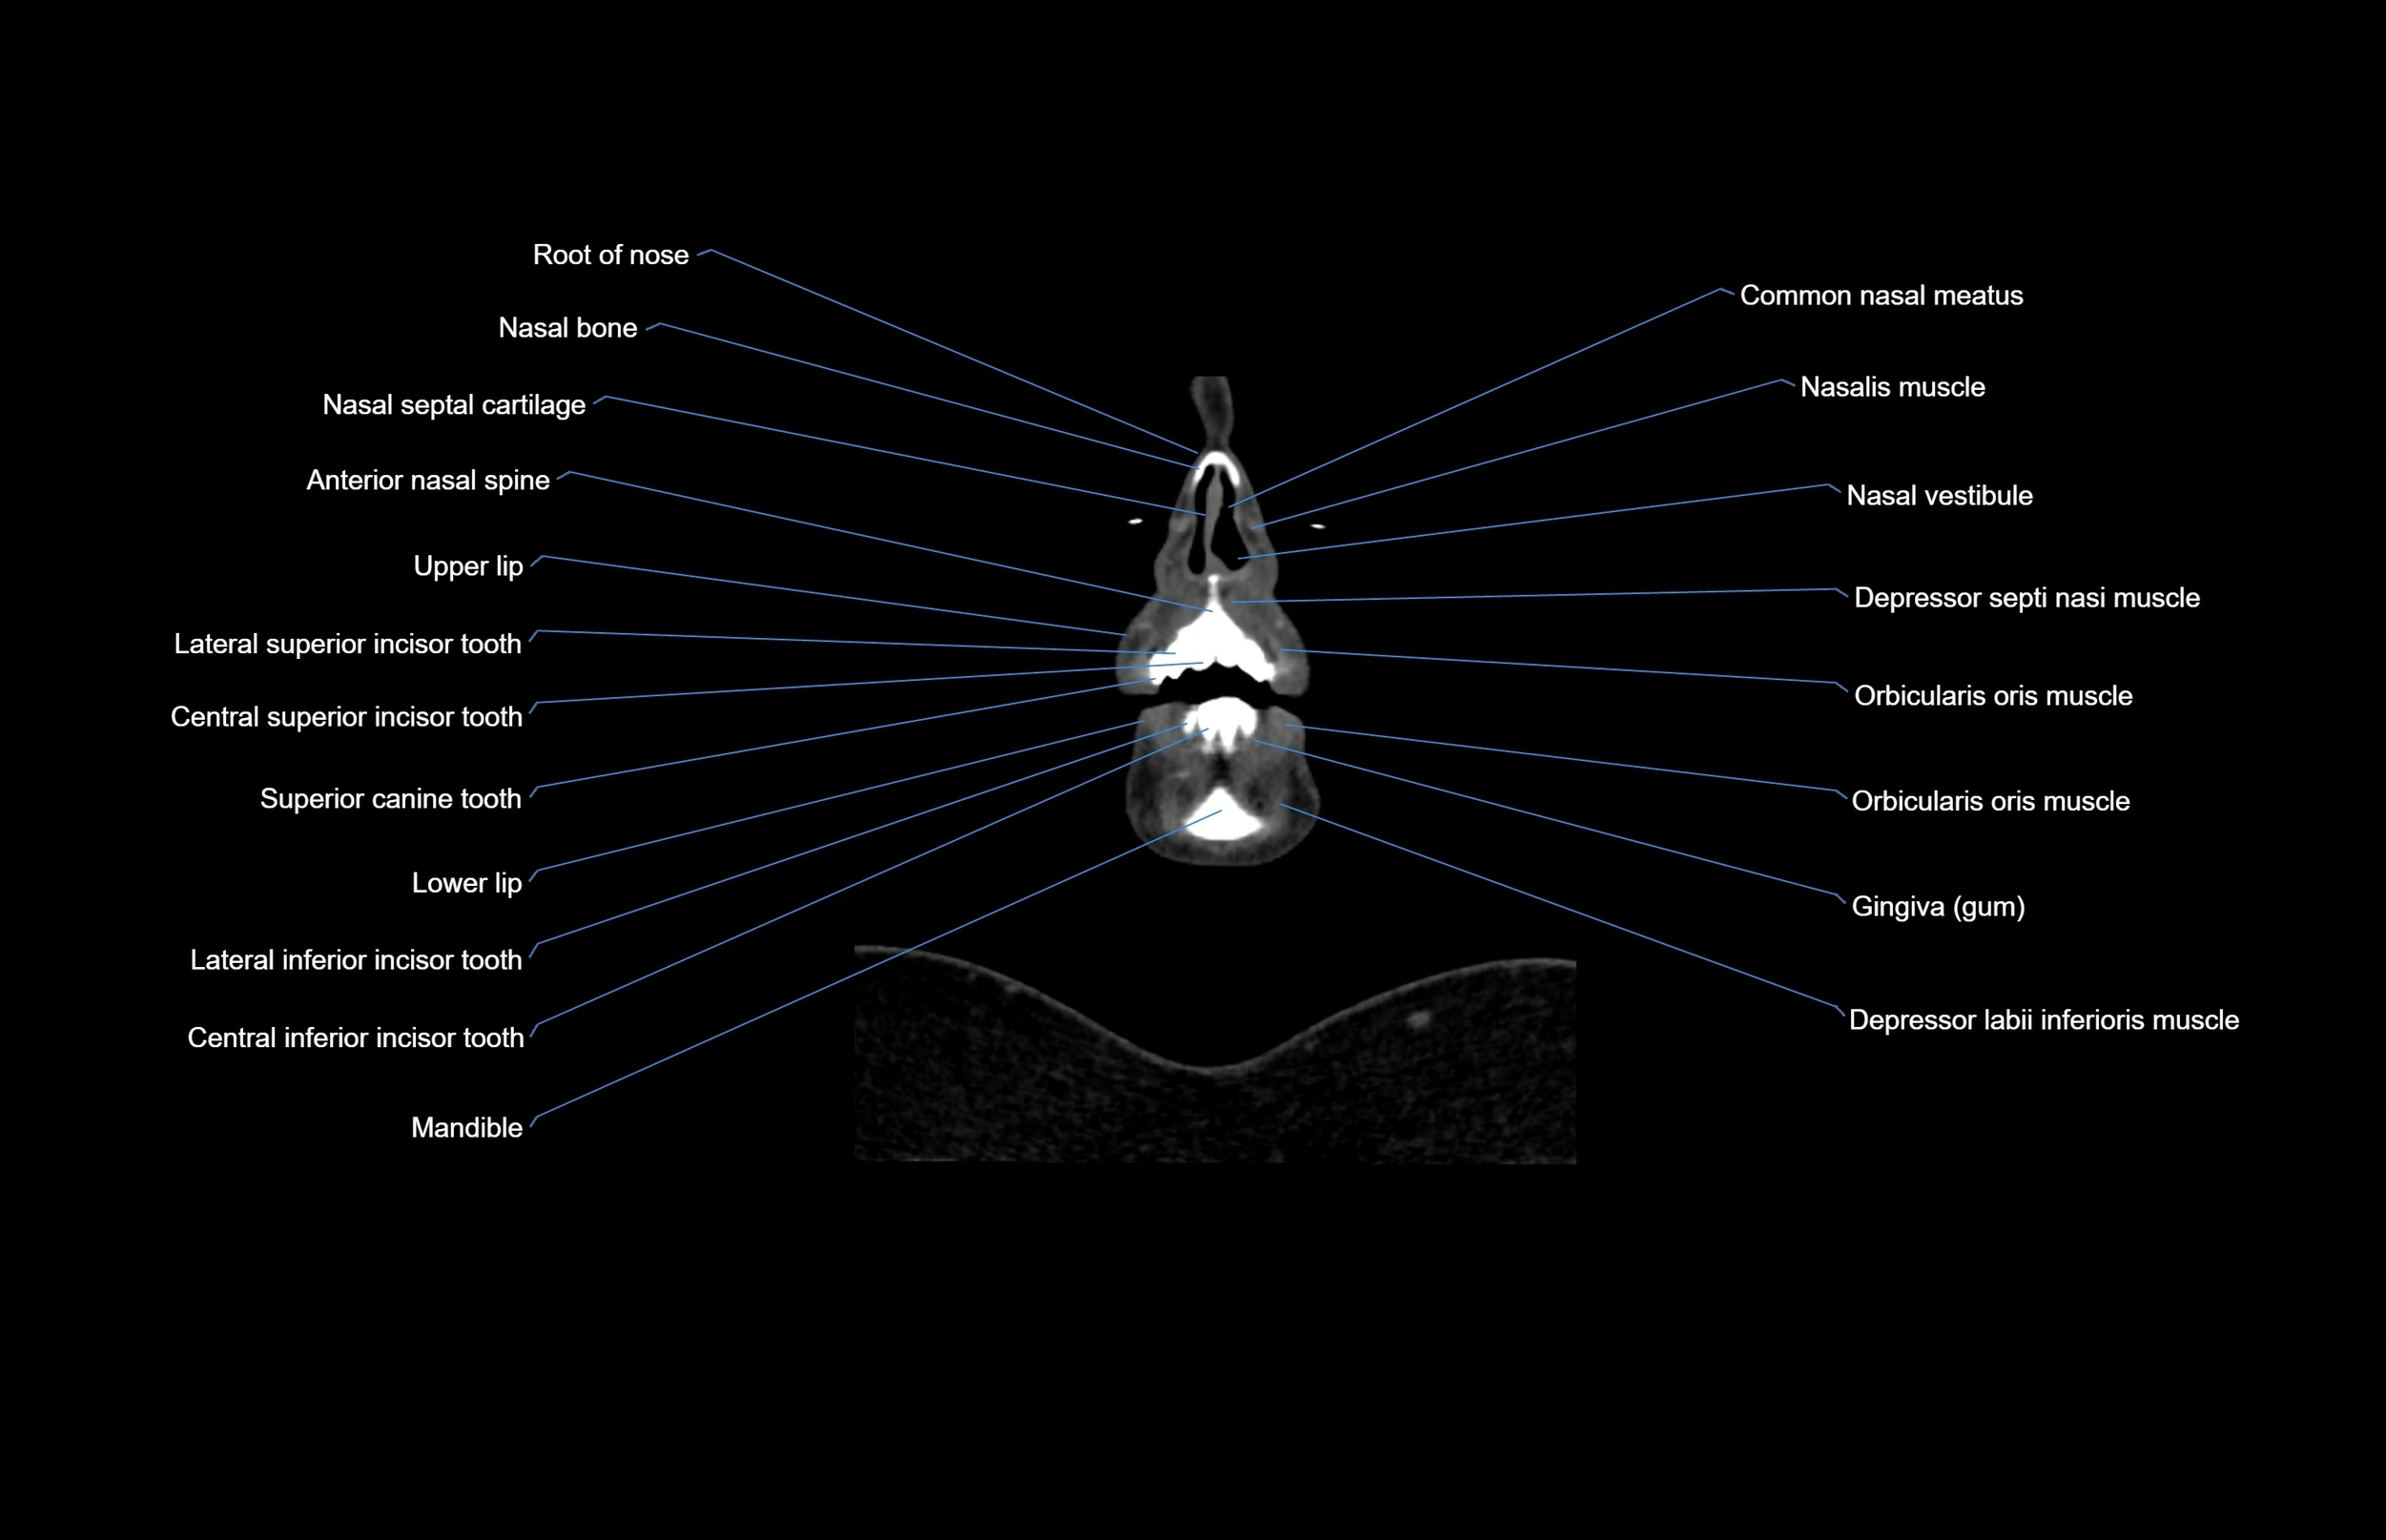

- Anterior nasal spine

- Common nasal meatus

- Depressor labii inferioris muscle

- Depressor septi nasi muscle

- Lateral inferior incisor tooth

- Lateral superior incisor tooth

- Lower lip

- Mandible

- Nasal bones

- Nasal vestibule

- Nasalis muscle

- Orbicularis oris muscle